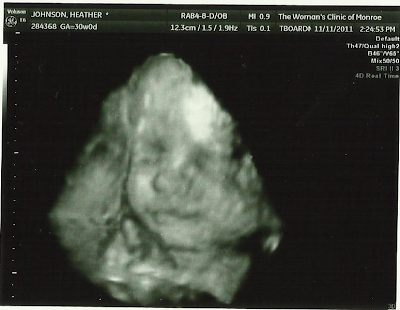

My stomach keeps growing and growing, and now you can notice substantial growth from week to week! I am at 34 weeks today! My due date is January 20, but if Little One has not made his entrance before the 18th of January, he will be induced. So technically, I only have 5 weeks and 5 days left!